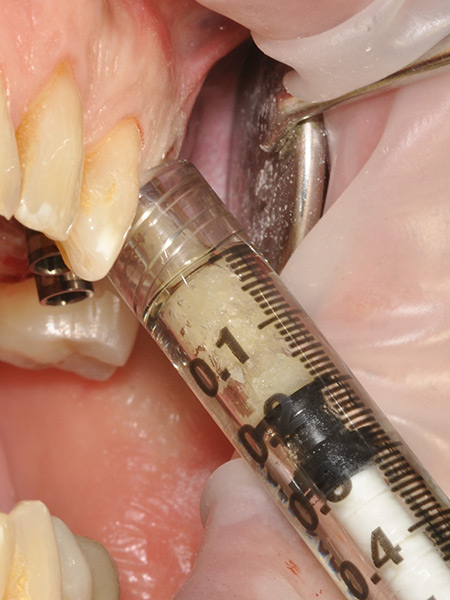

L’intervento ha previsto la progettazione di un impianto a carico immediato con sviluppo protesico digitale. Nello specifico, sono stati utilizzati i seguenti strumenti e tecnologie:

- Librerie aperte fornite da AZ Implant

L’intervento è stato eseguito dal Dr. Alessando Casolino (Bologna) dello Studio del Dr. Casolino e la protesi è a cura dell’Odt. Massimo Venerato (Lab odontotecnico C.P. Dental) su MUA tipo A dritti dell’altezza di 1 mm.